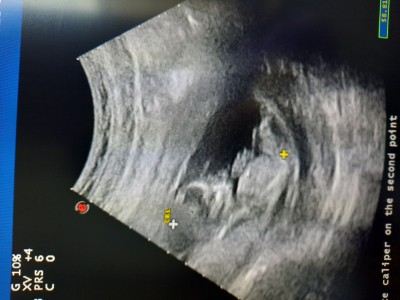

Merhaba. 12. Haftalikken aldim bu goruntuyu tahmin yapabilir misiniz rica etsem.

Gebelik haftası 14+3